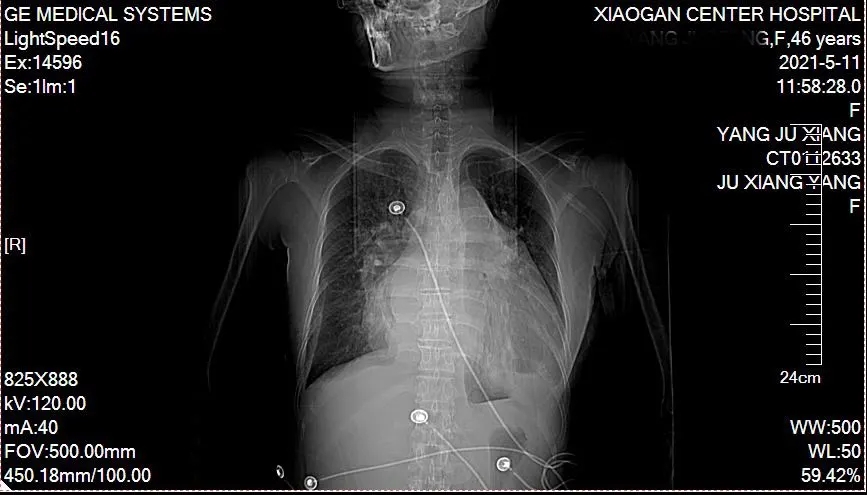

先天性心脏病患者,简单说就是心脏上多长了个“心眼”,这可能是件要命的事儿。来自孝南的46岁的杨女士,最近上腹胀痛不适,活动后出现心累,气促不适,自己觉得年纪不大,但活动耐力大不如以前,休息后可稍微缓解,来本院就医,收治感染科,入院后完善影像学检查,确诊为先天性心脏病:动脉导管未闭,心功能不全,心率失常。杨女士这才回忆到自己儿童时医生就听到心脏杂音,建议手术治疗,但患者恐惧心脏手术,同时担心手术的巨大费用,一直拖延到现在。

经心内科会诊,药物调整心功能好转后,杨女士随即被转入心胸外科,为患者进行体格检查完善相关辅助检查,根据患者的临床指征,科室团队进行了严谨细致的病情分析和讨论,决定患者可以不用开胸手术,建议为患者在局麻下实施介入封堵术。

整个手术在局部皮肤浸润麻醉下完成,手术刀口:右大腿根部两个小针眼。整个过程近60分钟,术后患者生命体征稳定,24小时后即可下床活动,术后3天复查心超,左心室舒张末期内径由6.50cm缩小到5.90cm,症状明显改善,并且办理出院。